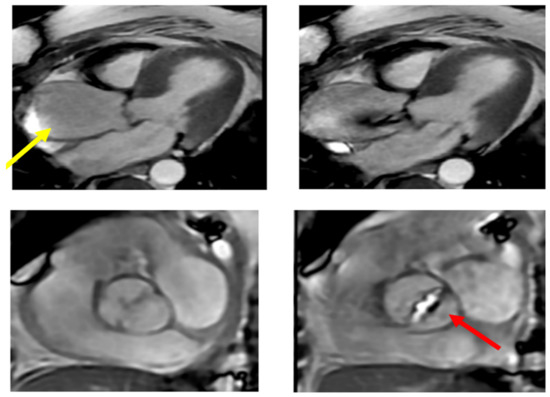

7.3. Magnetic Resonance

The contribution of the MR is relevant in those cases in which the echocardiography cannot estimate the morphology of the aortic valve and root and the diameter of ascending aorta and arch (Figure 9). It also has a complementary role in determining the aortic wall structure and the viability of myocardial muscle. It has a main role in determining scarry zones inside a healthy myocardium and the efficiency of cardiac chambers. EF may be estimate with this technique. These features should be matched with other decision elements derived from other imaging techniques to identify the proper surgical indication and forecast the patients’ prognosis. These factors make MR more useful in clinical practice than CT scan regarding functional evaluation [98] (Figure 9).

Figure 9.

Calcific bicuspid aorta Sievert Type 2 with fusion of the two coronary cusps for a raphe (red arrow). The patient had a transvalvular gradient of 40 mmHg. The ascending thoracic aorta is dilated above the Valsalva sinuses with a maximum diameter of 53 mm measured at the intersection with the right pulmonary artery (yellow arrow).